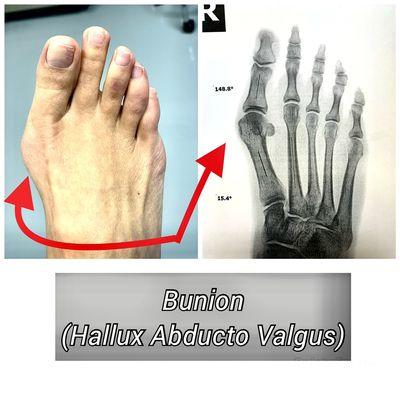

With a commitment to excellence, our dedicated staff ensures your comfort and swift attention from the moment you walk through our doors. Specializing in a range of services from bunion surgery to MLS laser therapy, we offer a comprehensive approach to addressing various foot and ankle conditions. For a glimpse into the transformative results we achieve, explore our before and after surgery photo gallery. Trust us to be your steadfast partner in restoring your mobility and well-being.